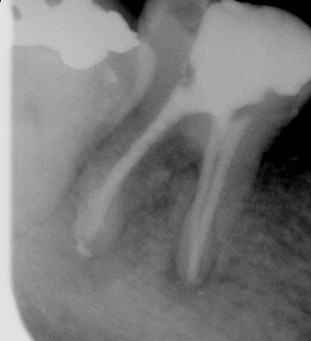

根管治療の術前・術後 Sさん

根管治療 前

根管治療 後

(左)神経が腐って根の外まで、炎症が波及しています(黒い影になっています)

(右)根の先の影も小さくなり、白いお薬を入れました